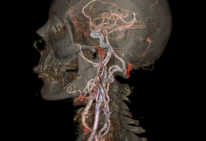

Gruesome and marvelous animated GIFs from GE's new body scanner

See gruesome and marvelous animated GIFs from GE's new body scanner http://www.theverge.com/2015/1/11/7527809/ge-ct-scanner

See gruesome and marvelous animated GIFs from GE's new body scanner http://t.co/p7Vvaq5Ayv pic.twitter.com/eaw3wPwVxs